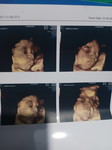

หม่่ามี๊ of 2 สุดน่ารัก คุณชาย